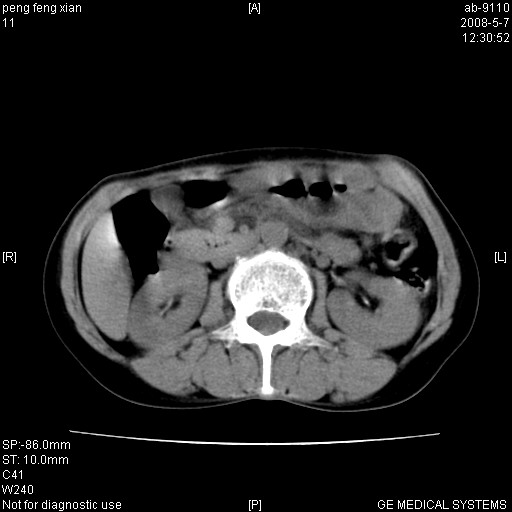

女,56岁。b超左一腹包块,考虑胃肠道肿瘤。

结肠病变?建议行全消化道检查!

胃体部胃壁增厚,不均匀性强化,与胰腺分解欠情.

考虑:胃癌,胰腺受侵待除外.